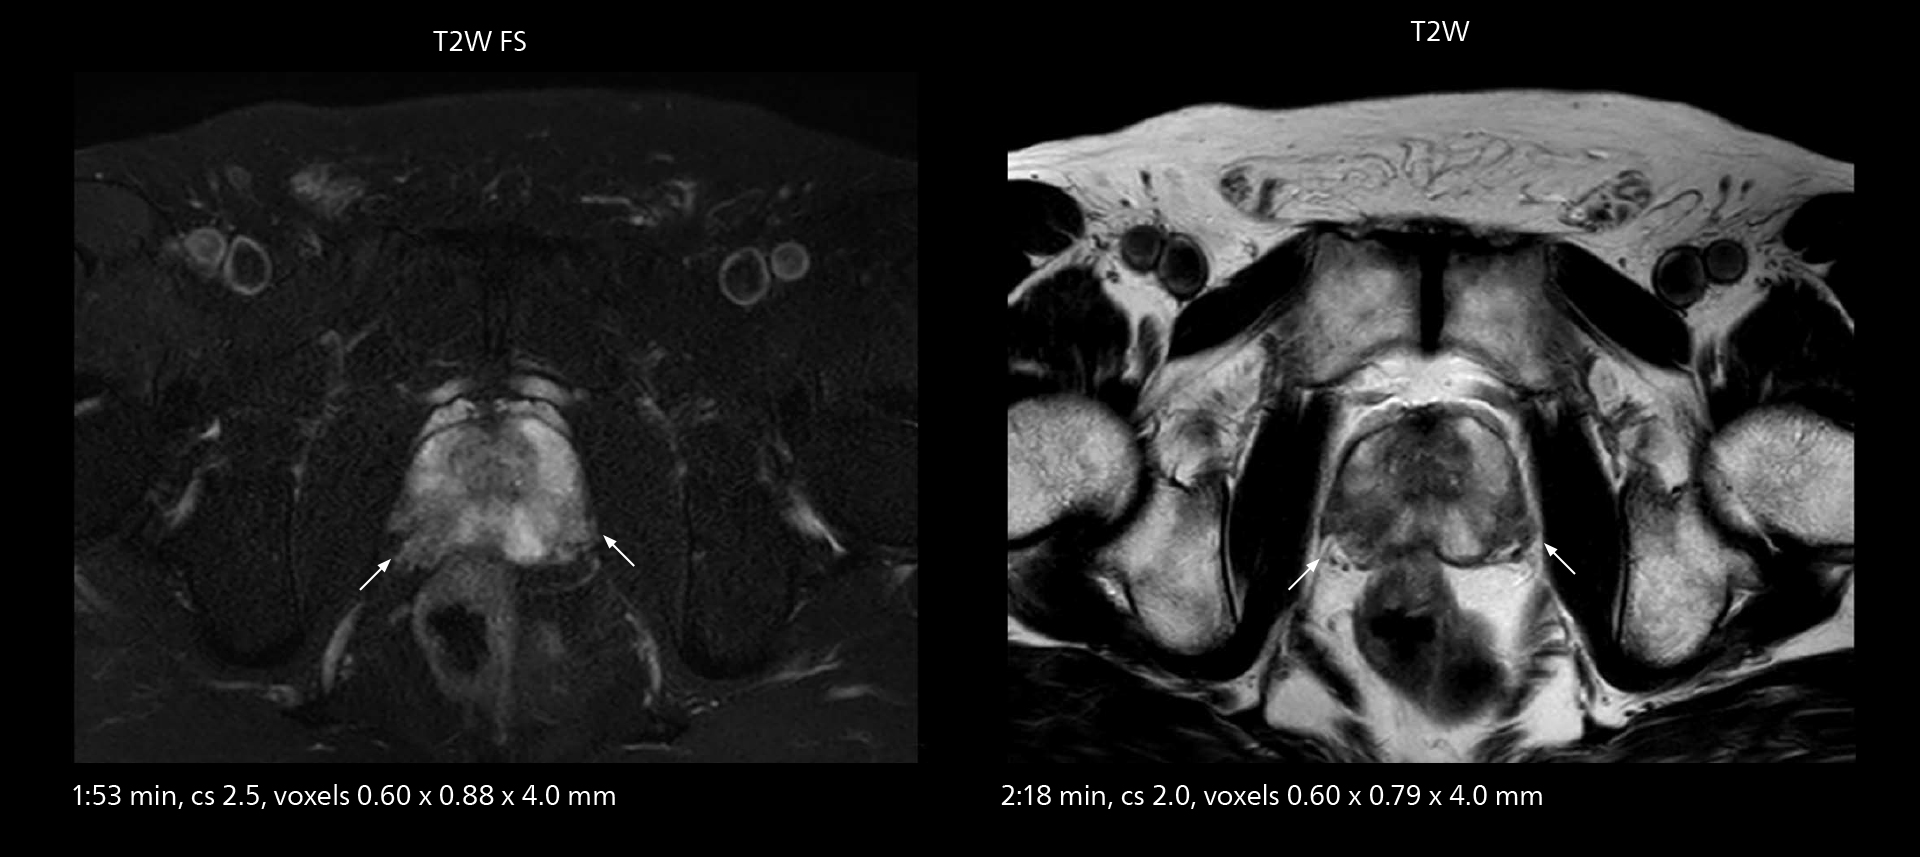

The high performance of the Vega HP gradients is particularly impressive in DWI. “The Vega HP gradients enable us to scan faster and use b-values as high as 2000, for example in prostate DWI and in DWIBS, which provides image quality that is remarkably improved over the previous system and we are able to more easily see lesions.”

Examples of prostate imaging showing faster scan times and improved resolution illustrate the power of SmartPath to Elition X in this case of prostate cancer with PI-RADS score 4.